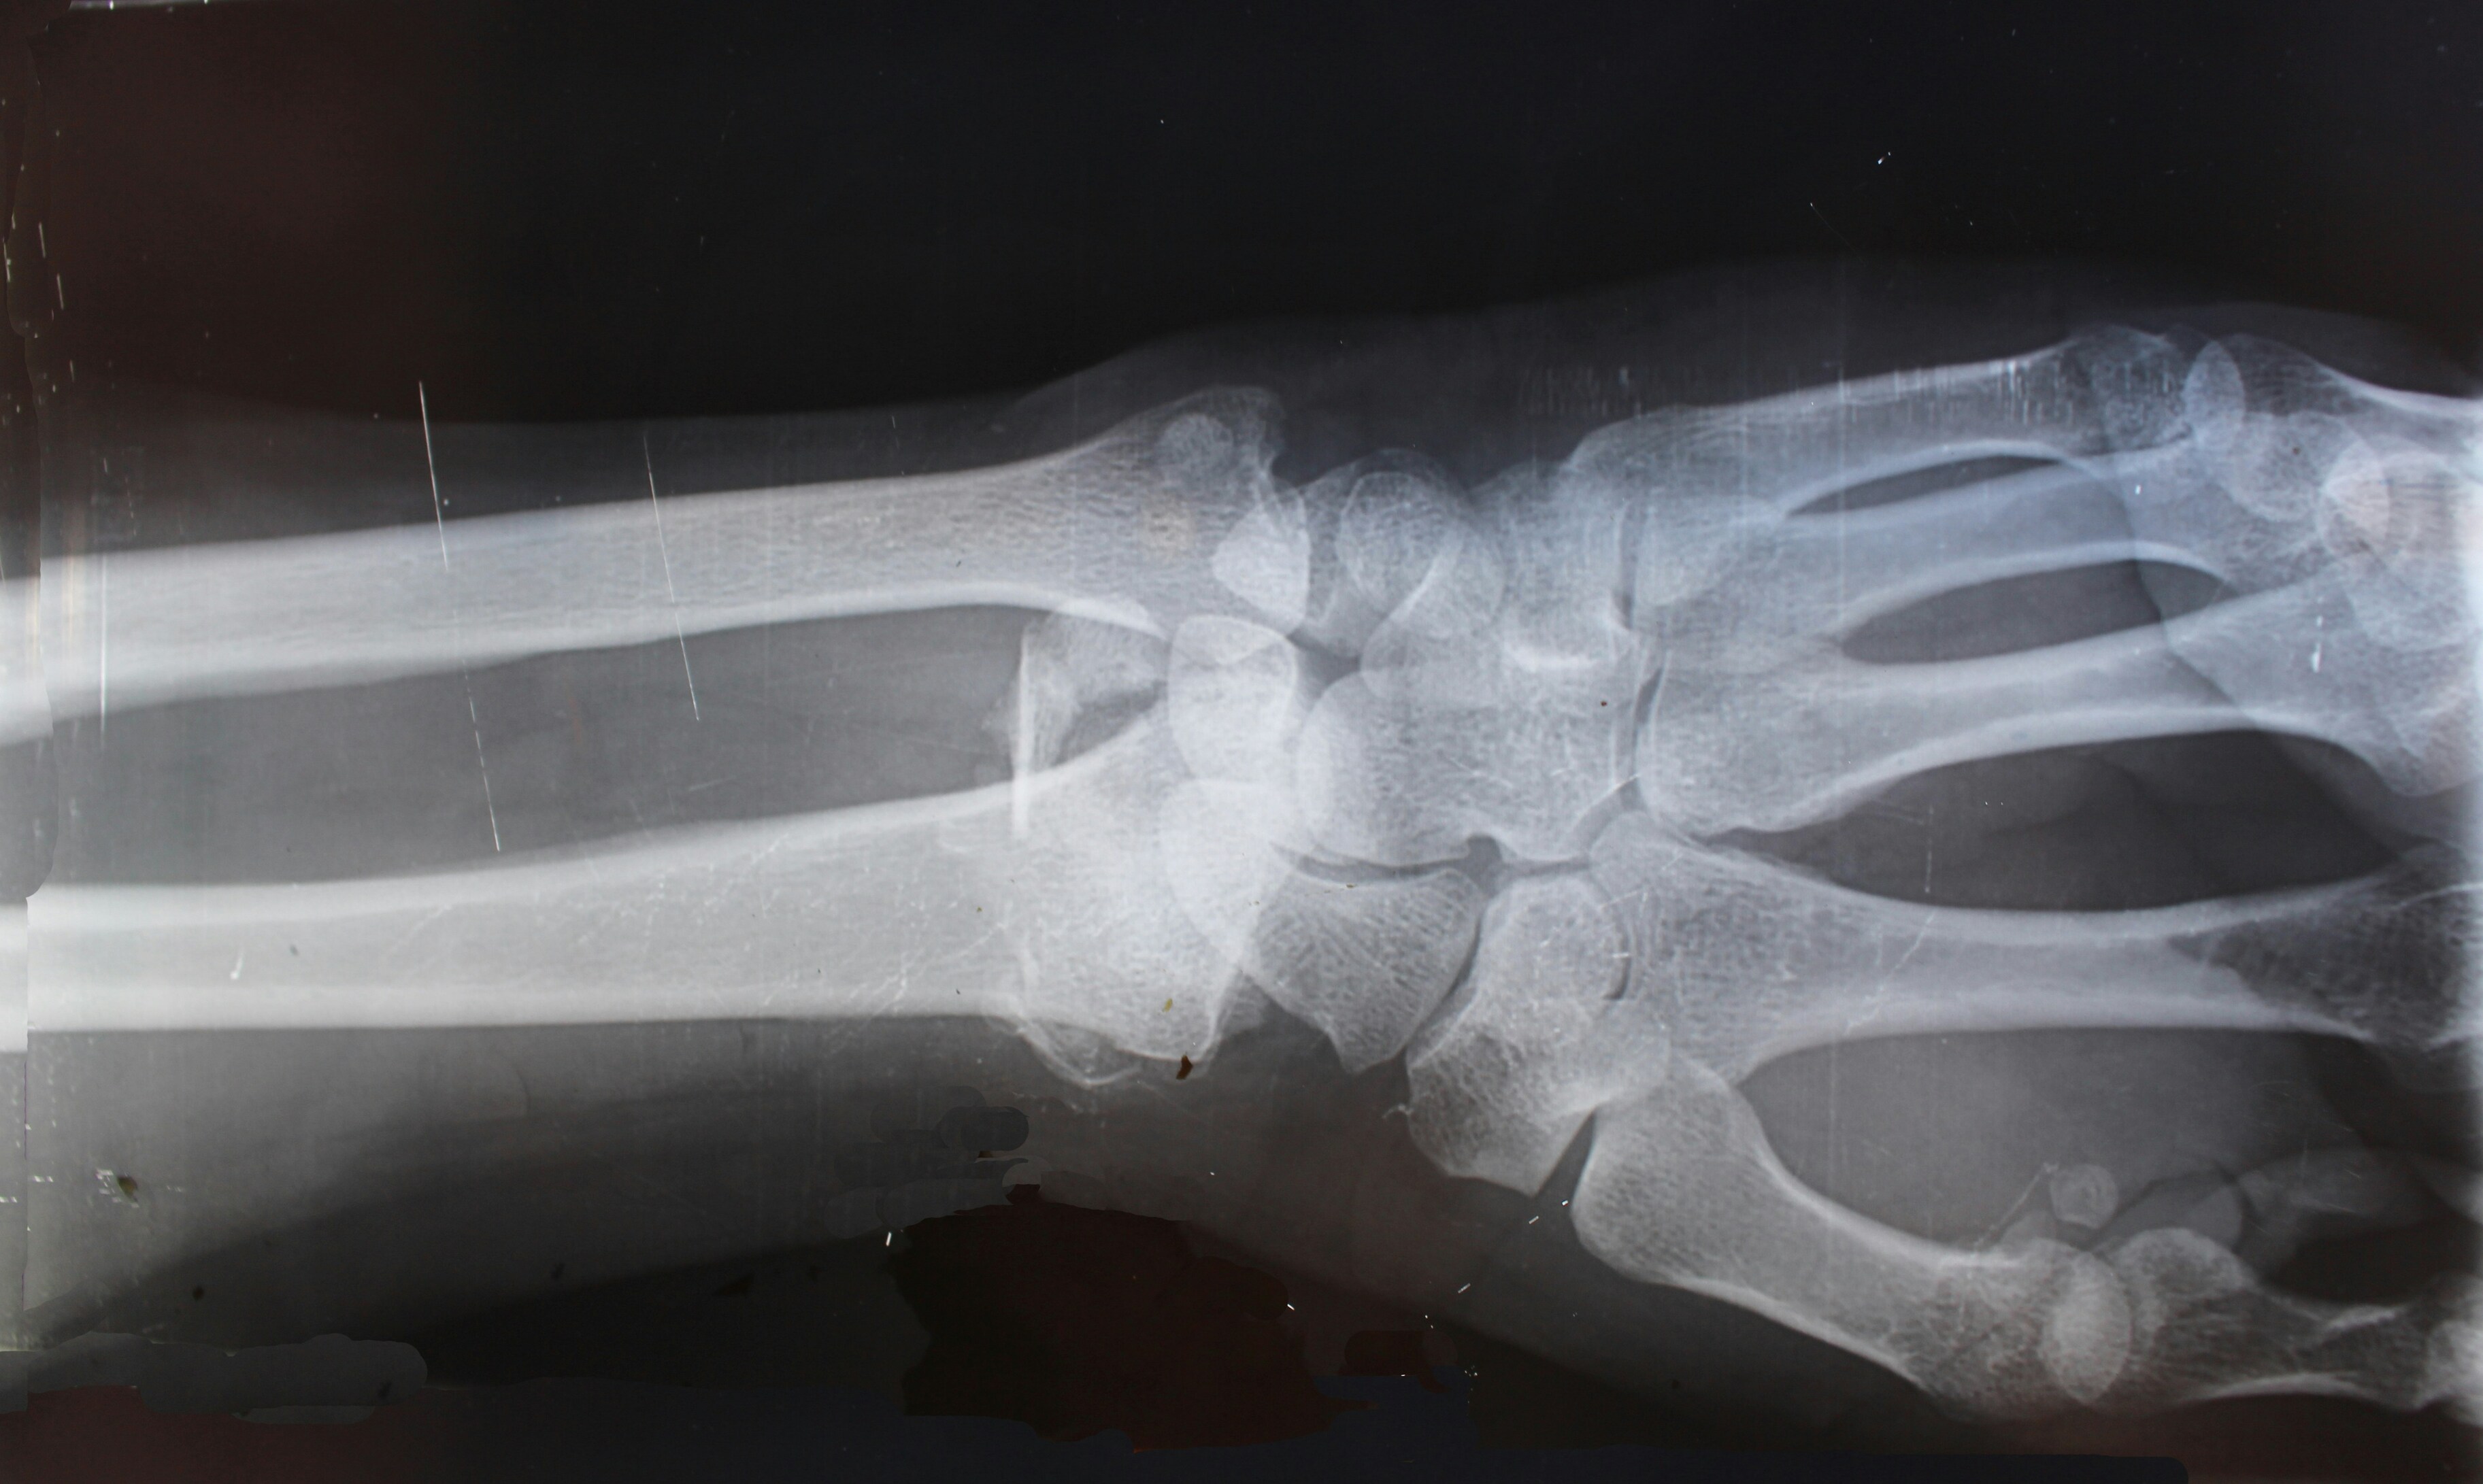

«Альгометрия» — это не единственный в своём роде эксперимент. Один из самых известных эффектов длительного пребывания в космосе — это потеря костной и мышечной массы: в условиях невесомости мышцы меньше напрягаются, а кости теряют плотность.

Эксперименты в этой области помогают разработать методы профилактики и лечения остеопороза и саркопении.